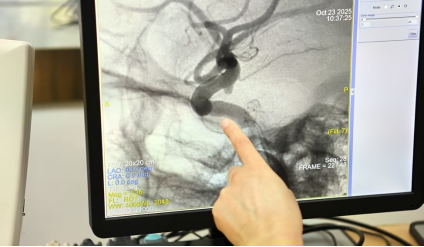

面对这样的“定时炸弹”,刘俊开展了5000余例脑动脉瘤手术。他创新性地应用复合手术再通术式,使动脉瘤夹闭术的成功率大幅提升。在手术中,刘俊手持器械在毫米级的空间内操作,汗水顺着额角滑落却不让手有半分颤抖。他凭借精湛技艺实现了高达96%的治愈率。